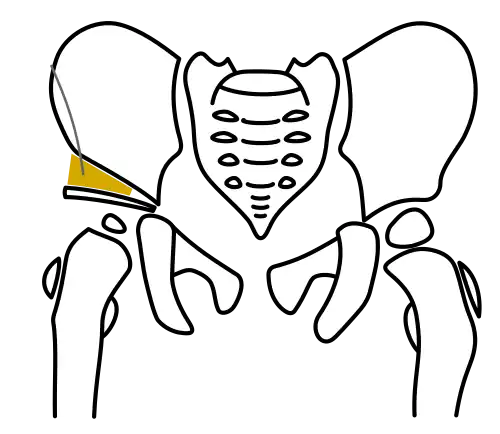

Acetabuloplasty, Step 3: Insertion of the bone wedge

Acetabuloplasty, Step 3: Insertion of the bone wedge -

In both techniques, a suitably shaped bone wedge is inserted into the resulting gap under X-ray guidance. If needed, the wedge can be fixed with an osteosynthesis wire (Kirschner wire). The procedure typically takes 45 to 60 minutes for an experienced surgeon.[3][11]

Bone wedge

Using autologous bone from the patient is challenging in children. When an intertrochanteric correction is performed simultaneously, the trimmed bone wedge may be used, but it is often too small. Donor bone from bone banks or harvested femoral heads from joint replacement surgeries is commonly used. Donor bones are disinfected and deproteinized in certified thermal disinfection devices and cryopreserved at -20°C or sterilized in an autoclave with pressurized steam or gamma rays. These processes adhere to strict regulations by the German Medical Association, Medical Devices Act, and Robert Koch Institute.[12][13]